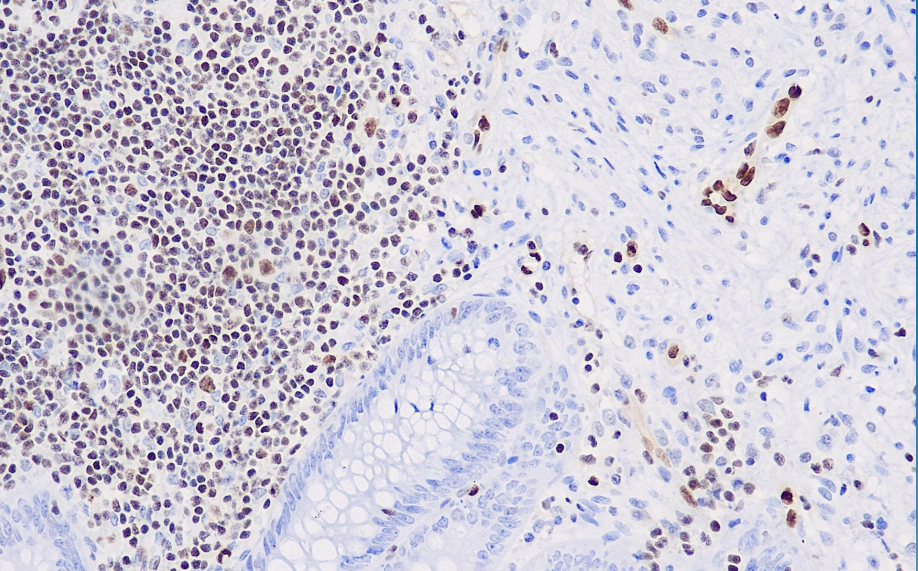

Positive control: appendix

The FLI-1 gene and FLI-1 protein are recognized for their important role in the pathogenesis of Ewing sarcoma/peripheral neuroblastoma (ES/PNET). FLI-1 was initially applied to the study of Ewing sarcoma/peripheral primitive neuroectodermal tumors, demonstrating superior specificity and sensitivity compared to CD99. Recent studies have confirmed that the FLI-1 gene also plays an important role in the embryonic development of blood vessels, with expression observed in endothelial cells of various types of human vascular structures (arteries, veins, and lymphatic vessels), achieving a positivity rate of up to 90% in angiosarcomas; it is also expressed in lymphoblastic lymphoma. This antibody is now recommended for use in combination with CD99 to identify Ewing's sarcoma/peripheral neuroectodermal tumor (ES/PNET); it is also used in the study of vascular endothelial tumors, particularly in distinguishing between epithelial-like vascular endothelial tumors and epithelial tumors.

FLI-1 antibody reagents can specifically bind to FLI-1 molecular antigens. Immunohistochemistry kits containing FLI-1 antibody reagents are suitable for the precise diagnosis of Ewing's sarcoma/peripheral primitive neuroectodermal tumors.